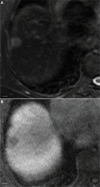

Hepatocellular carcinoma (HCC) is one of the most common primary hepatic malignancies and one of the fastest-growing causes of cancer-related mortality in the United States. The molecular basis of HCC carcinogenesis has not been clearly identified. Among the molecular signaling pathways implicated in the pathogenesis of HCC, the Wnt/β-catenin signaling pathway is one of the most frequently activated. A great effort is under way to clearly understand the role of this pathway in the pathogenesis of HCC and its role in the transition from chronic liver diseases, including viral hepatitis, to hepatocellular adenomas (HCAs) and HCCs and its targetability in novel therapies. In this article, we review the role of the β-catenin pathway in hepatocarcinogenesis and progression from chronic inflammation to HCC, the novel potential treatments targeting the pathway and its prognostic role in HCC patients, as well as the imaging features of HCC and their association with aberrant activation of the pathway.